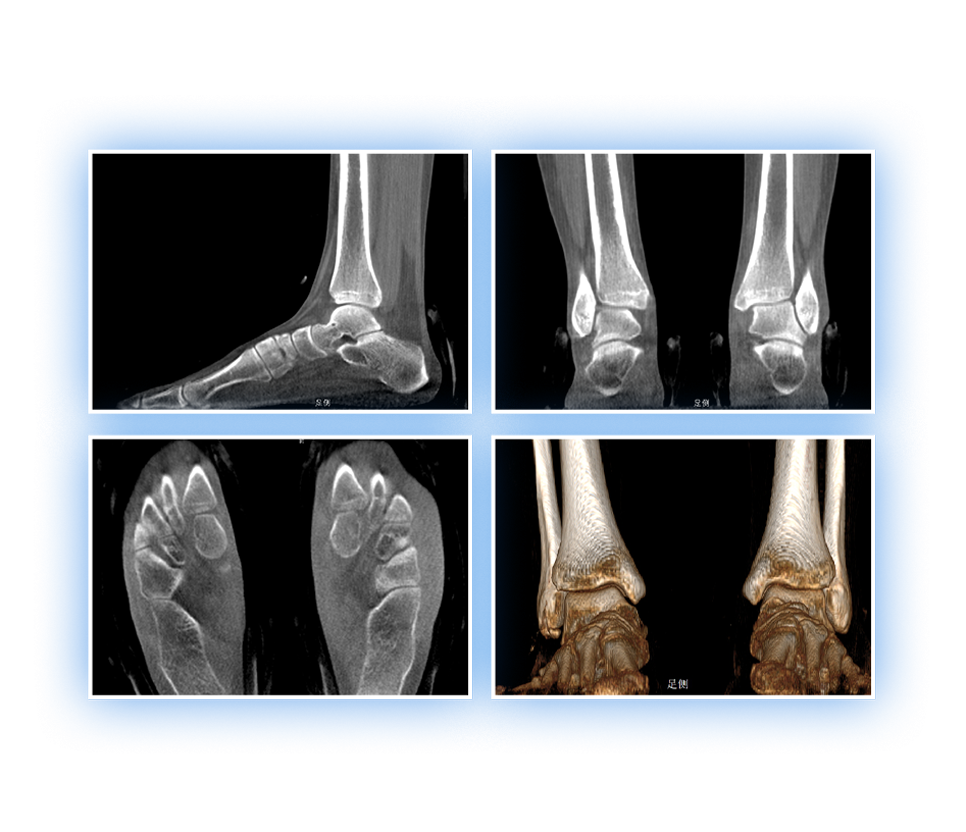

足踝

精准诊断

手术方案规划

术后随访

VR体绘制重建